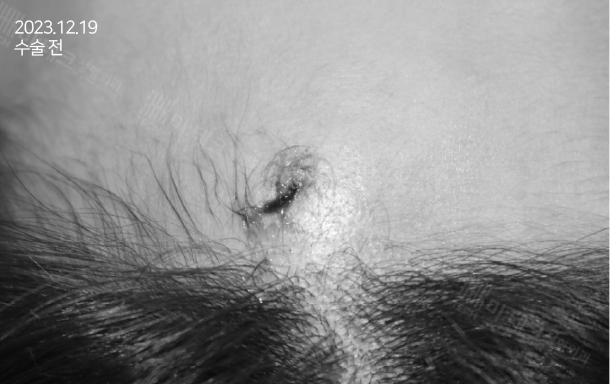

* 본 포스팅은 피지낭종, 지방종 등의 양성종양 및 치료 성형 증례에 대한 내용으로 다소 거부감을 느낄 수 있는

사진과 동영상들이 포함되어 있으니 비위가 약하신 분들은 주의하시기 바랍니다